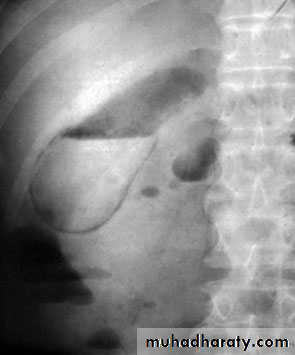

54Gas in the gall bladder and gall bladder wall(Clostridium perfringens). Emergency surgery is indicated.

Al-Madena copy